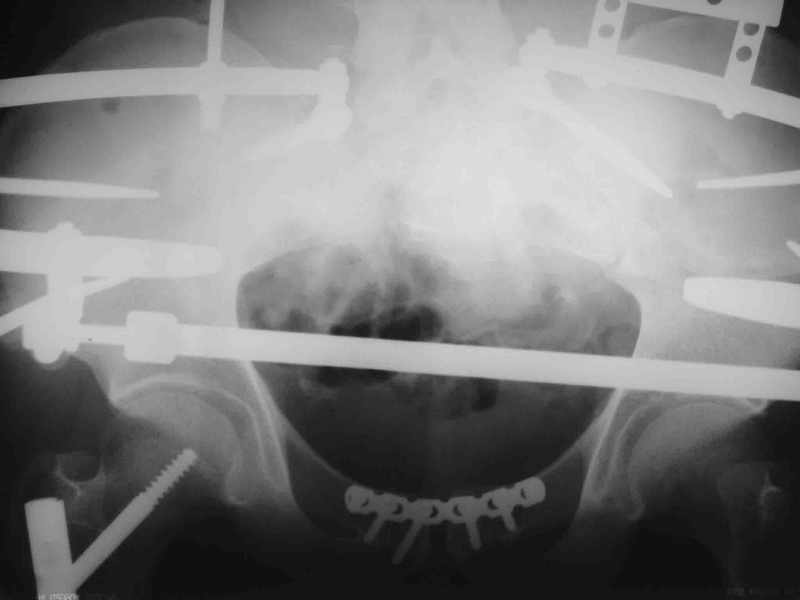

Вот вариант решения похожей ситуации